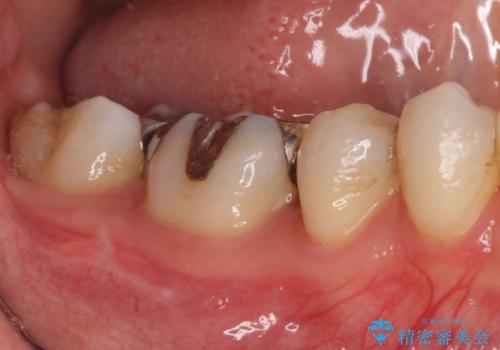

- 虫歯の治療を主訴に来院されました。

奥歯は不可逆性歯髄炎の診断のもと、根管治療を行なった後、被せ物の治療を行なっております。

根管治療を行なった歯は被せ物を使用することで、破折しづらくなります。